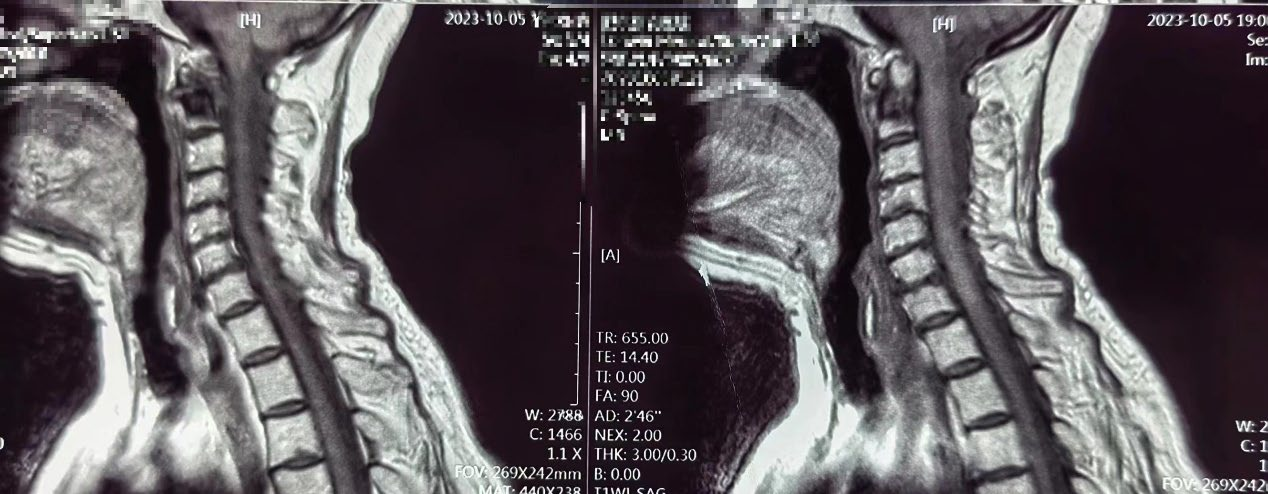

3月12日,疼痛科王立奎和陈家骅教授团队成功完成了一例老年患者的寰椎(第一颈椎)骨水泥注射术。患者为 80 岁女性,因“颈枕部疼痛8月加重2月余”就诊于我院疼痛科。患者表现为抬头后右侧后枕部疼痛明显。该患者每次下地活动20分钟后就必须平卧,正常生活起居受到极大影响。经检查患者系寰椎存在血管瘤占位,累及整个右侧寰椎侧块。

在完善相关检查后,团队采用自制的骨水泥注射针,在CT导航下完成了患者的寰椎骨水泥注射成形术。术后在王春霞护士长的护理团队的配合下,目前患者症状明显缓解,正常生活起居不再受限。患者对科室的治疗护理非常满意。

我院疼痛科自 2000 年开展该项技术以来,累计完成近3000例该类手术。与传统技术不同的是,科室采用的是CT导航下穿刺,能更清晰地显示椎体周围解剖结构,轴位成像使得上胸椎及颈椎的穿刺更具安全性和准确性。手术在局部麻醉方式下进行,对患者年龄及身体一般情况要求相对较低。且因为CT导航的精确性,骨水泥可精准注射到病变靶点,从而更安全更高效的解决患者不适症状。